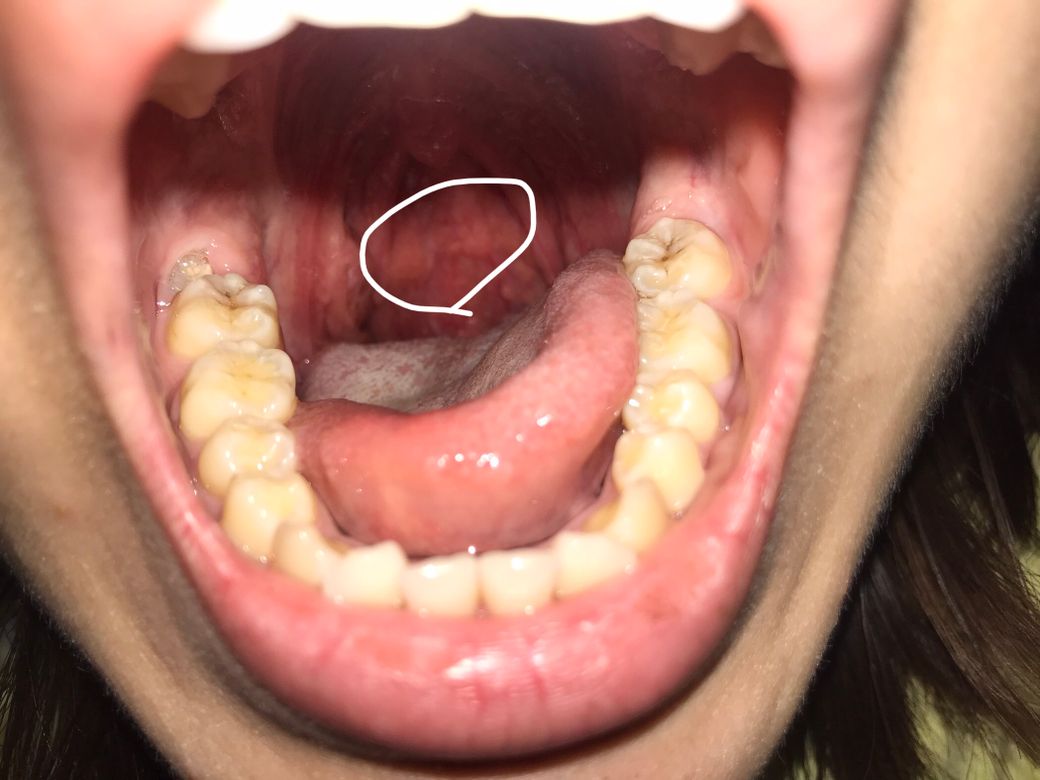

목 후레쉬 비춰서 봤는데 혹시 부은 건가요..?

아니면 혹? 이런건 아니죠..? 좀 부어올라 보여서요 ㅠㅠㅠㅠ 목에 이물감이 느껴져서 보니까 목구멍이 부어보여서요 원래 이런건지 뭔지 해서요

노랗게 보이는 부분은 정상적인 림프조직이고, 이외 특별한 이상은 없어보입니다. 걱정되시면 근처 이비인후과를 방문해보시기 바랍니다.

특별한 문제가 있는 것은 아닙니다. 이물감이 있다면 약간 염증이 있어서 나타난 증상이라고 보시면 되고, 증상이 심하지 않다면 따뜻한 물을 자주 드시면서 지켜보시면 됩니다.